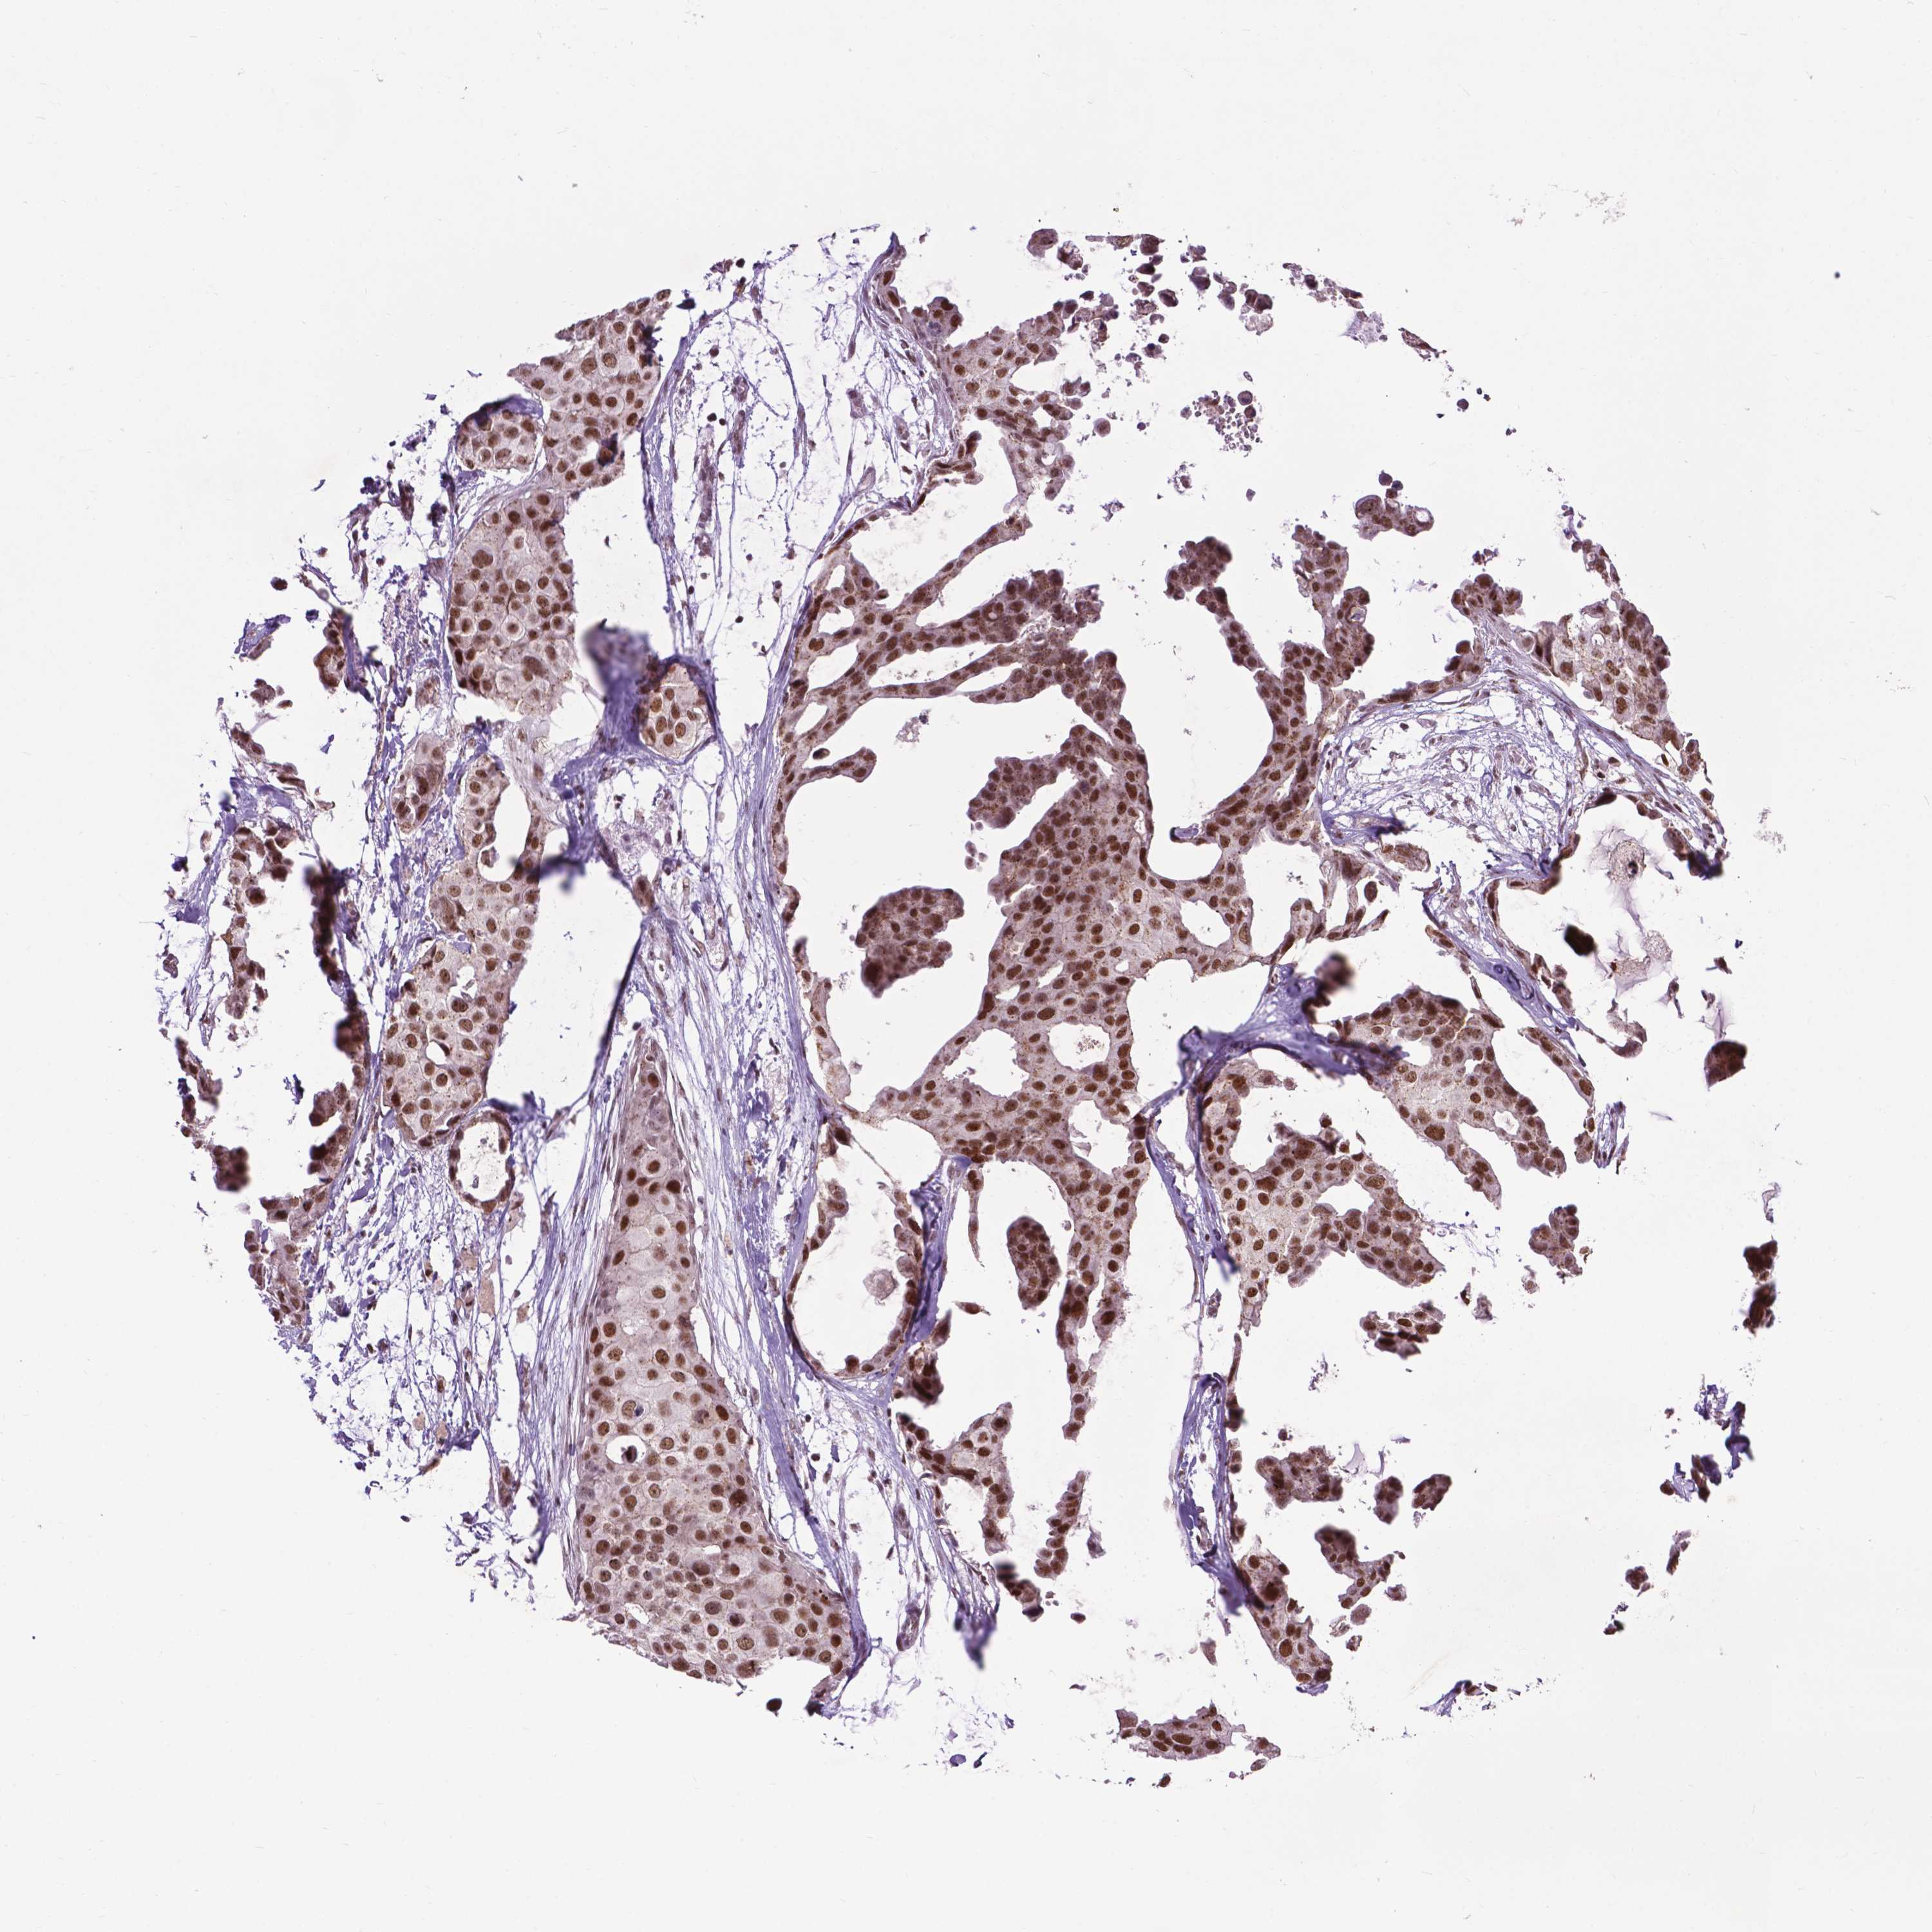

BRCA TCGA BRCA VALIDATION PROTEIN EXPRESSION

ANTIBODIES

AND

VALIDATION